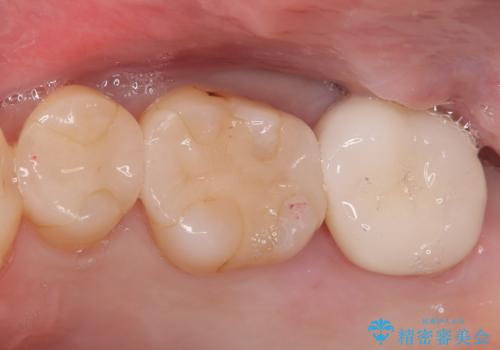

- 金属を外して白い歯を手に入れたいとのことで来院されました。

まとめて治療することで通院回数を減らすことができ、見た目も大変満足していただきました。